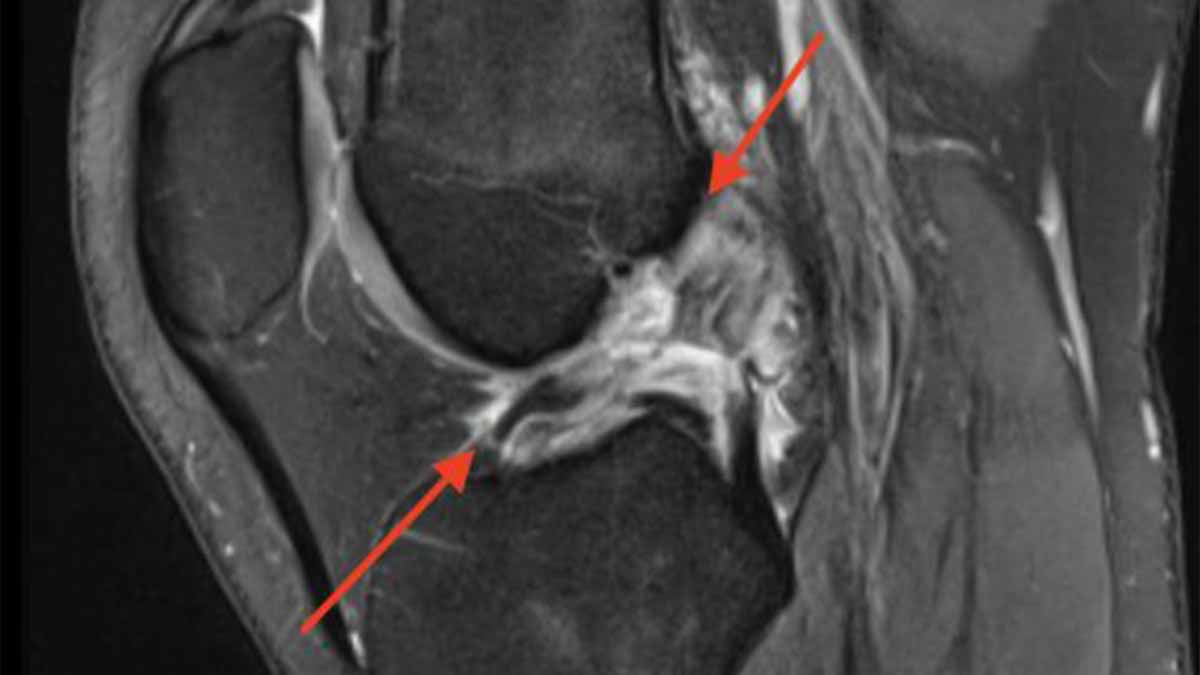

• MRI scan to confirm ligament tear

Diagnosis

Diagnosis is made using: